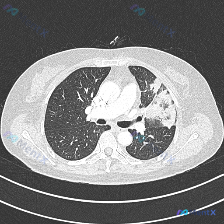

这是一份肺门水平的胸部CT肺窗横断面图像,图像质量良好,无伪影:

- 病变位置与形态:左肺上叶可见大片状、不均匀高密度实变影,伴随磨玻璃密度影,边界模糊,范围较大

- 关键征象:病变区域内可见明确的空气支气管征,也就是实变肺组织中可见含气的支气管分支影

- 其他评估:右肺野透亮度、肺纹理大致正常;左侧支气管近端通畅;左侧胸膜未见明确胸腔积液或明显胸膜增厚